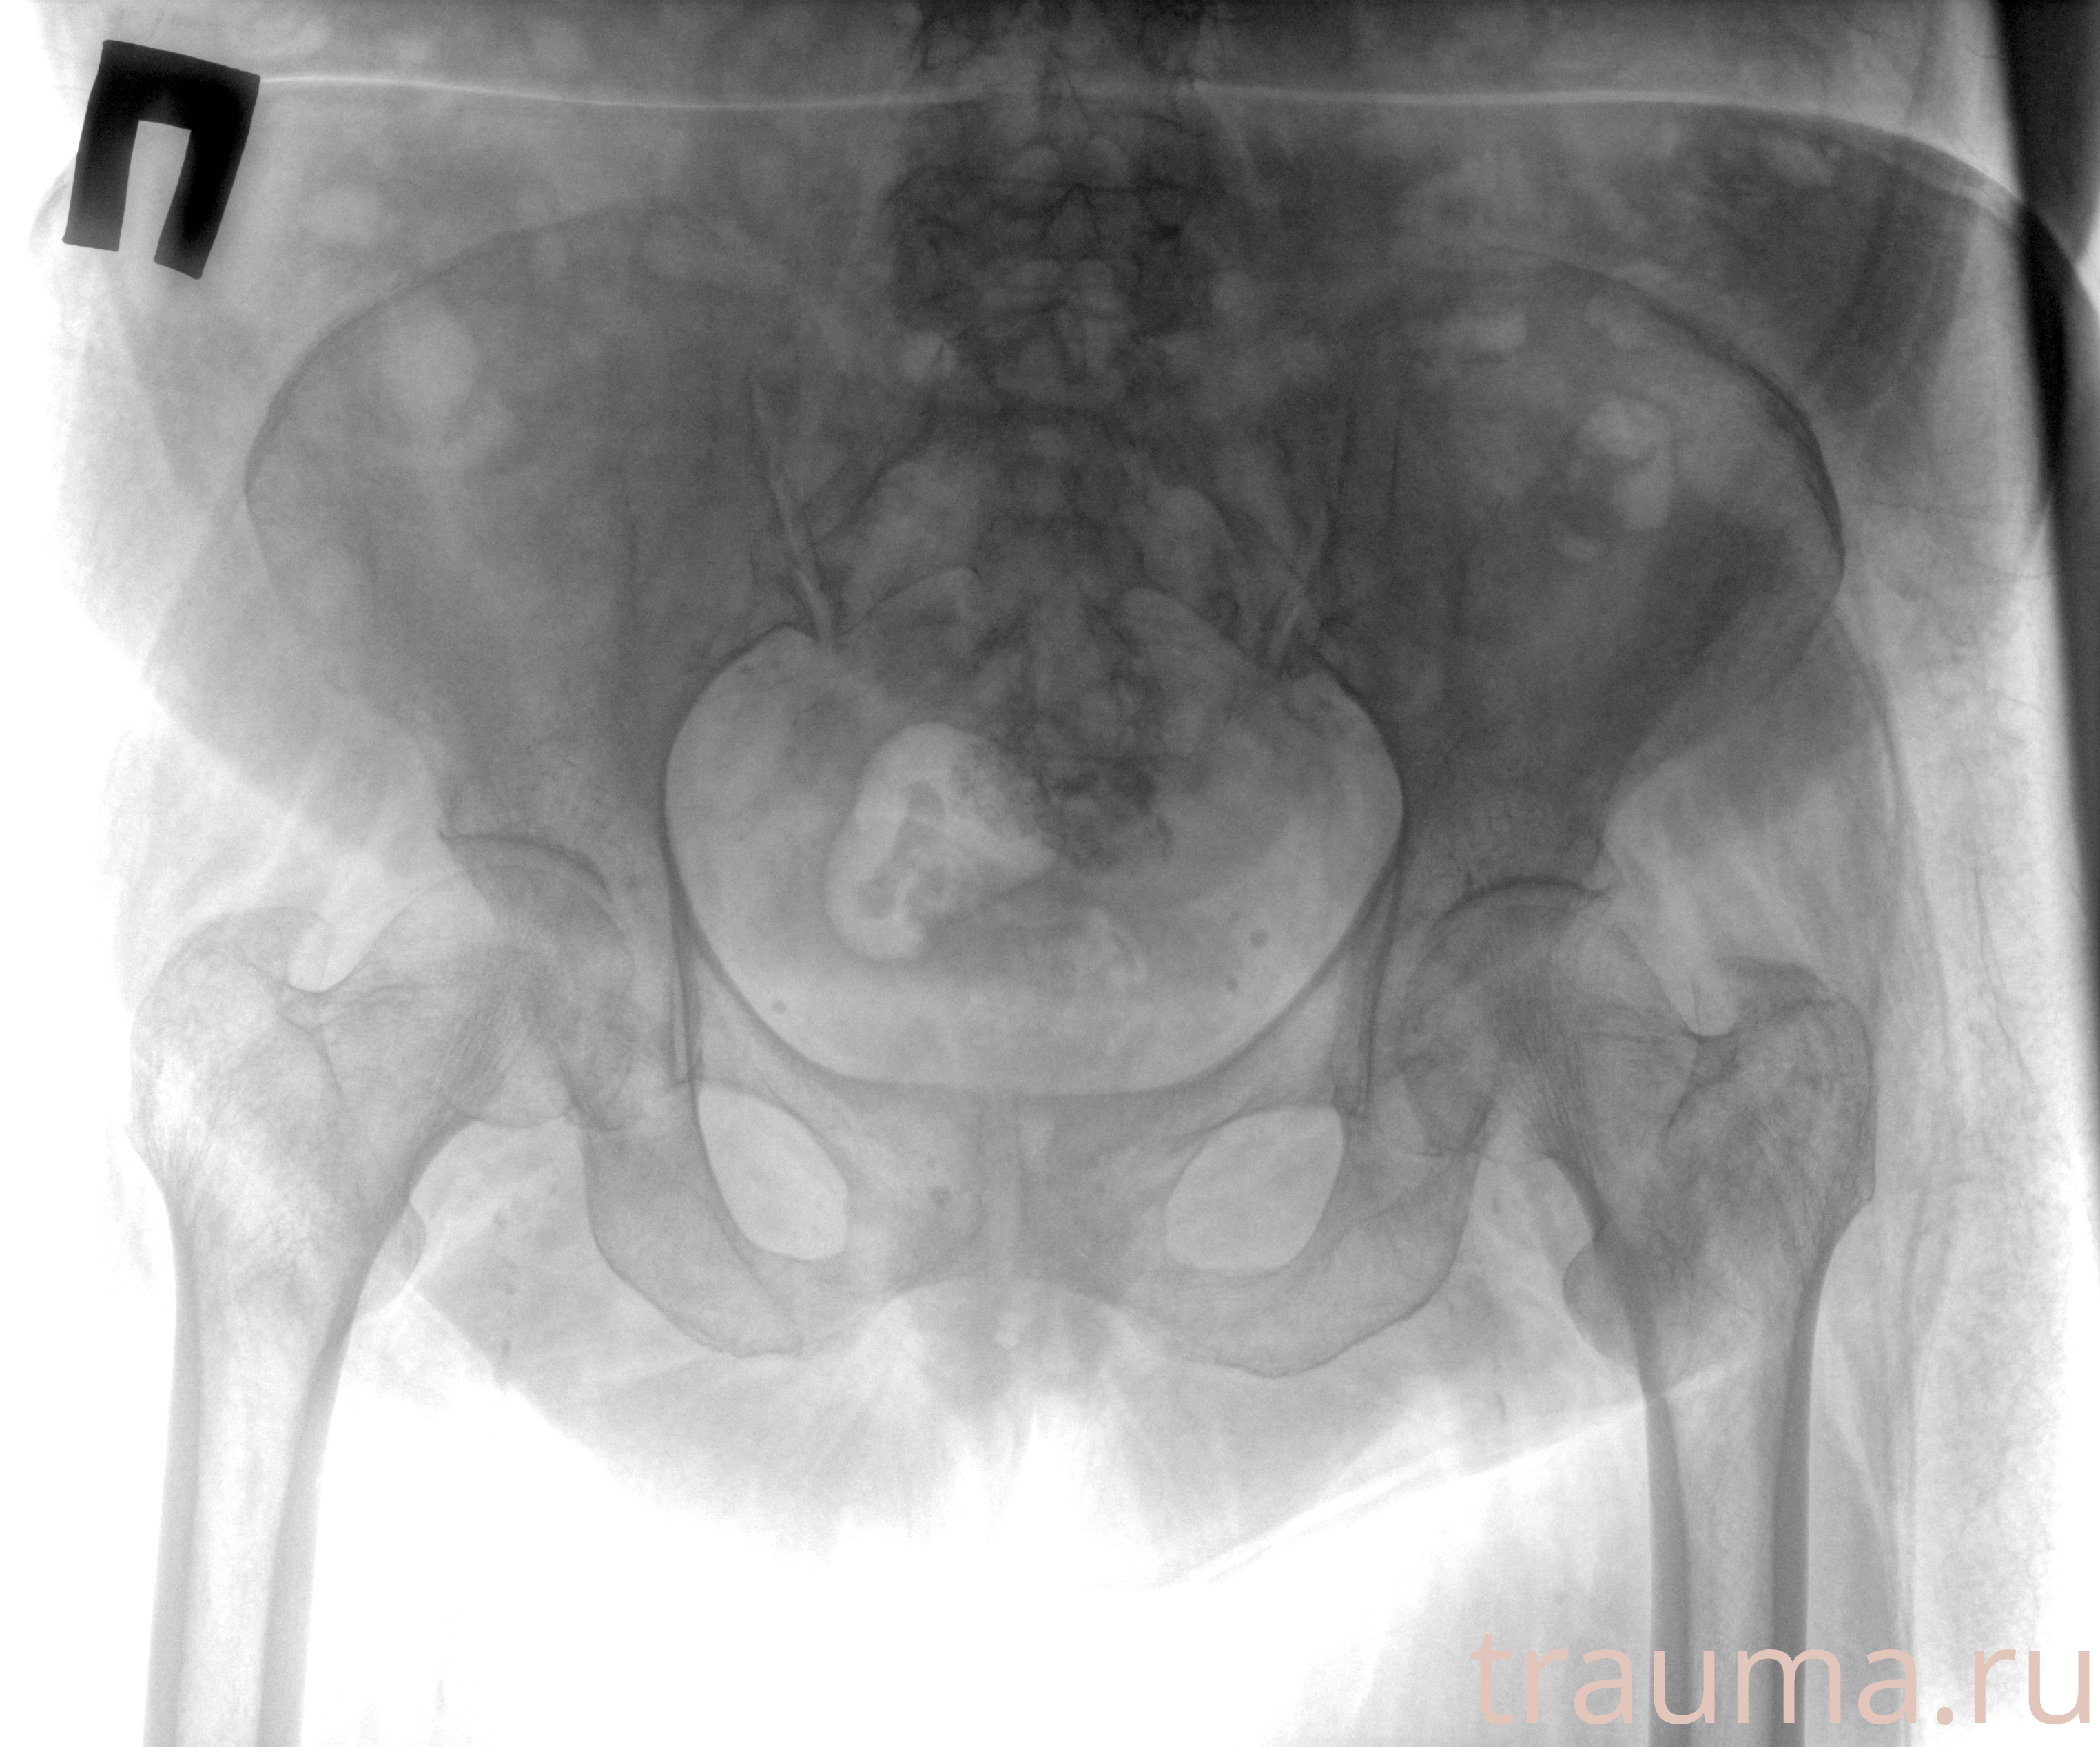

Рентгенограммы

Рентген на дому: по вашему адресу приезжает врач-рентгенолог, травматолог-ортопед с мобильным рентгеновским аппаратом, проводит диагностику травмы или заболевания, делает необходимые рентгенограммы, дает рекомендации по дальнейшему лечению. Получить качественные снимки в домашних условиях возможно благодаря уникальной методике, разработанной МосРентген Центром для института  Склифосовского

при переломе шейки бедра и пневмонии от компании МосРентген Центр - партнера Института имени Склифосовского